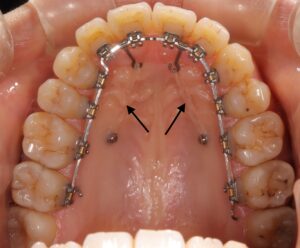

前回からの期間に、右下の奥歯の間隔が開いてしまいました。

この隙間をまた閉じていくために、右下の奥歯から前歯にかけてゴムを掛けました。

これで隙間が埋まるか様子を見ます。

上の歯は、上顎に掛けたゴムを交換したことで歯の動く痛みを感じました。